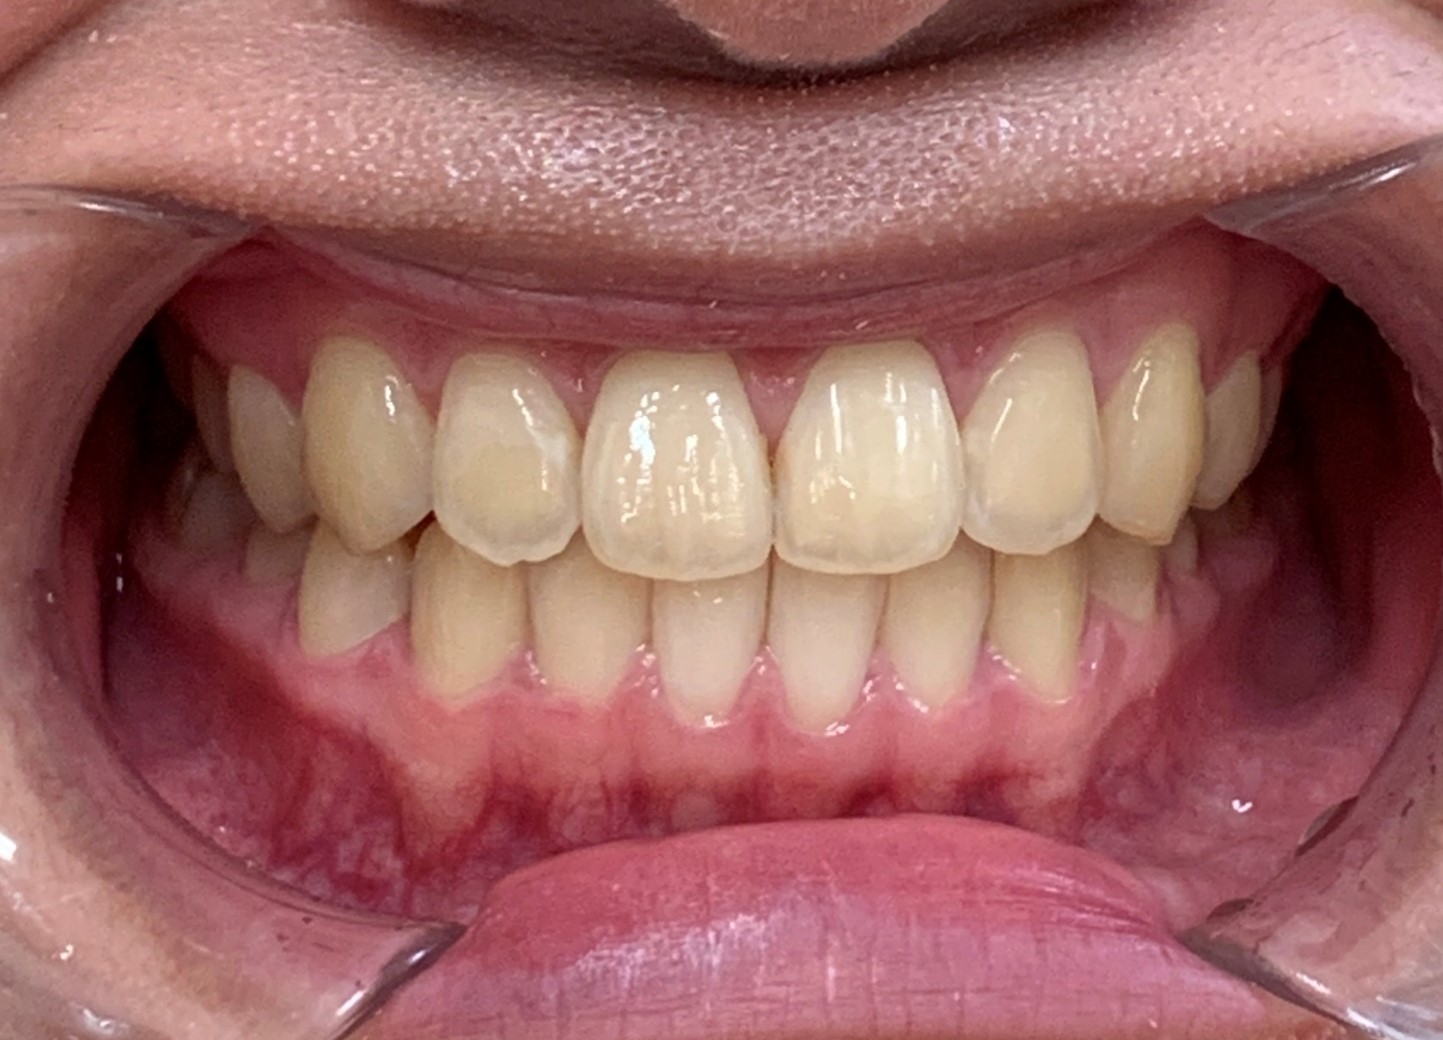

20代女性「下の前歯が上の前歯に被さっている」上下の歯の位置が逆になっている「反対咬合」を、マウスピース矯正装置「インビザラインGO」で費用を抑えて改善した症例

上下の前歯が正常な位置関係になり、美しい歯並びになりました。噛み合わせも問題ありません。

患者様にも「笑ったときに見た目が気にならなくなった」と非常にご満足いただいております。